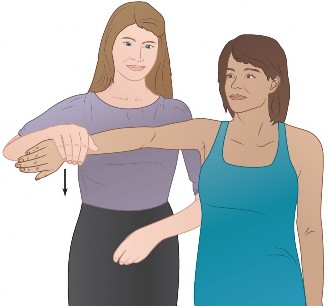

The correct answer is (C). Each RC tendon has specific tests for pathology. The supraspinatus strength test (aka Jobe test) is performed by abducting the shoulder to

90 degrees, bringing the arm in the scapular plane (30 degrees forward), and maximally internally rotating the arm (thumb pointing to the floor) (Fig. 2–1). The test is positive if weakness is found or if pain is experienced. Another test for the supraspinatus is the drop arm test. In the drop arm test, the arm is passively elevated by the examiner to the Jobe position, the patient is asked to attempt to keep it there, and the arm is released by the examiner. The test is positive if the patient is not able to keep the arm elevated and the arm drops.

Figure 2–1 Jobe test.